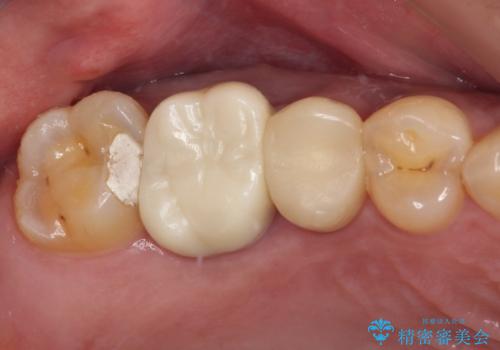

目立つ銀歯と欠けてしまった詰め物 オールセラミッククラウンでの補綴治療